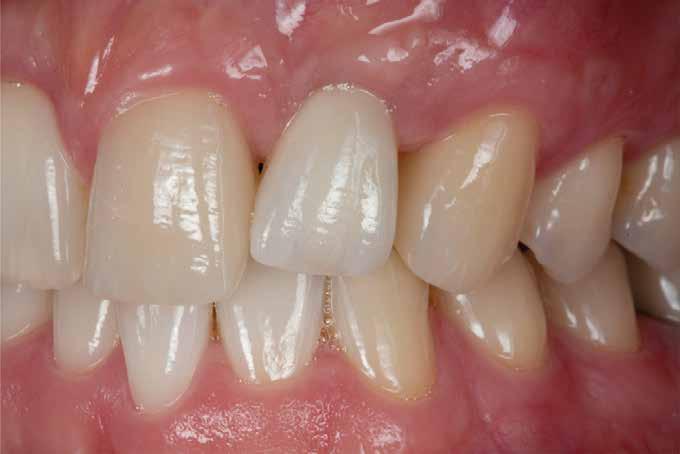

13. ábra: A végső szituáció 6 hónappal a teljes kerámia korona behelyezése után.

A helyreállító tervezésnek megfelelően 3,8 mm átmérőjű, 11 mm hosszúságú implantátum került behelyezésre a hat hónapos gyógyulási időszak után. Végül a cirkóniumfelépítményre teljes kerámia korona került.

A végeredmény képei egyértelműen bizonyítják, hogy a leírt augmentációs technikával egy igazán esztétikus eredményt lehet elérni. Forrás: Cosmetic Dentistry 2013/4